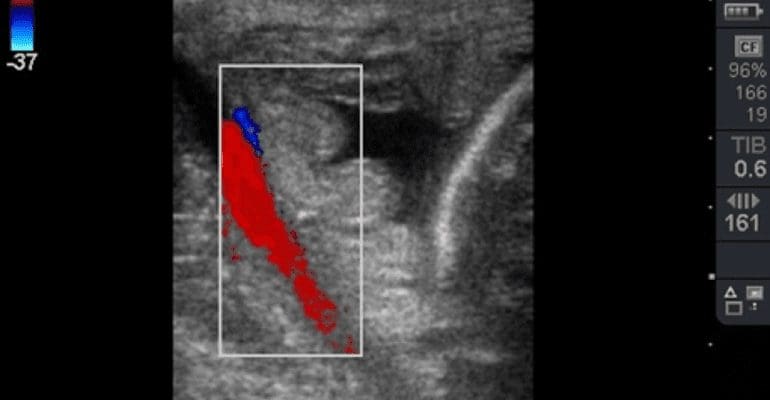

Fig. 1 Color Doppler image of the uterine artery used to ensure correct transducer placement for taking measurements of the combined thickness of the uterus and placenta (CTUP). Image courtesy of James Crabtree BVM&S CertEM(StudMed) MRCVS, Equine Reproductive Services (UK) Ltd.

Color Doppler is very useful in all species and in many clinical situations for giving an ‘overview’ of blood flow – its presence or absence, direction, and a semi-quantitative assessment of flow velocity. It can be useful to facilitate anatomical orientation such as in making measurements of the combined thickness of the uterus and placenta (CTUP) as a means of assessing placental health and the possible development of placentitis in mid-late gestation mares. It can be useful in assessing the likely nature of certain ovarian structures such as haemorrhagic anovulatory follicles (HAFs), and changes in color Doppler signal in pre-ovulatory follicles have been shown to drop off in the four hours prior to ovulation. It can also be applied in the transition period to assist decision-making about the likely ovulatory or anovulatory nature of dominant follicles.